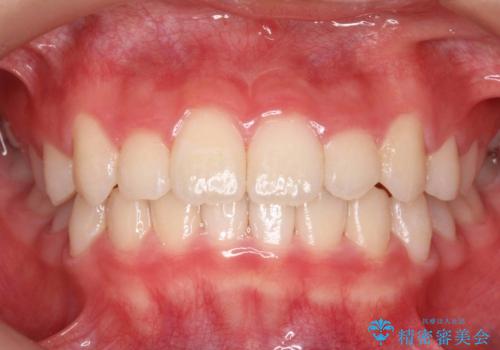

[ 前歯のねじれ・がたつき ] マウスピース矯正

![[ 前歯のねじれ・がたつき ] マウスピース矯正の症例 治療後](https://seimitsushinbi.jp/wp/wp-content/uploads/2024/02/e7a01485e4f4dd0da04705fde4cc34cc-500x350.jpg?v=1708502585)